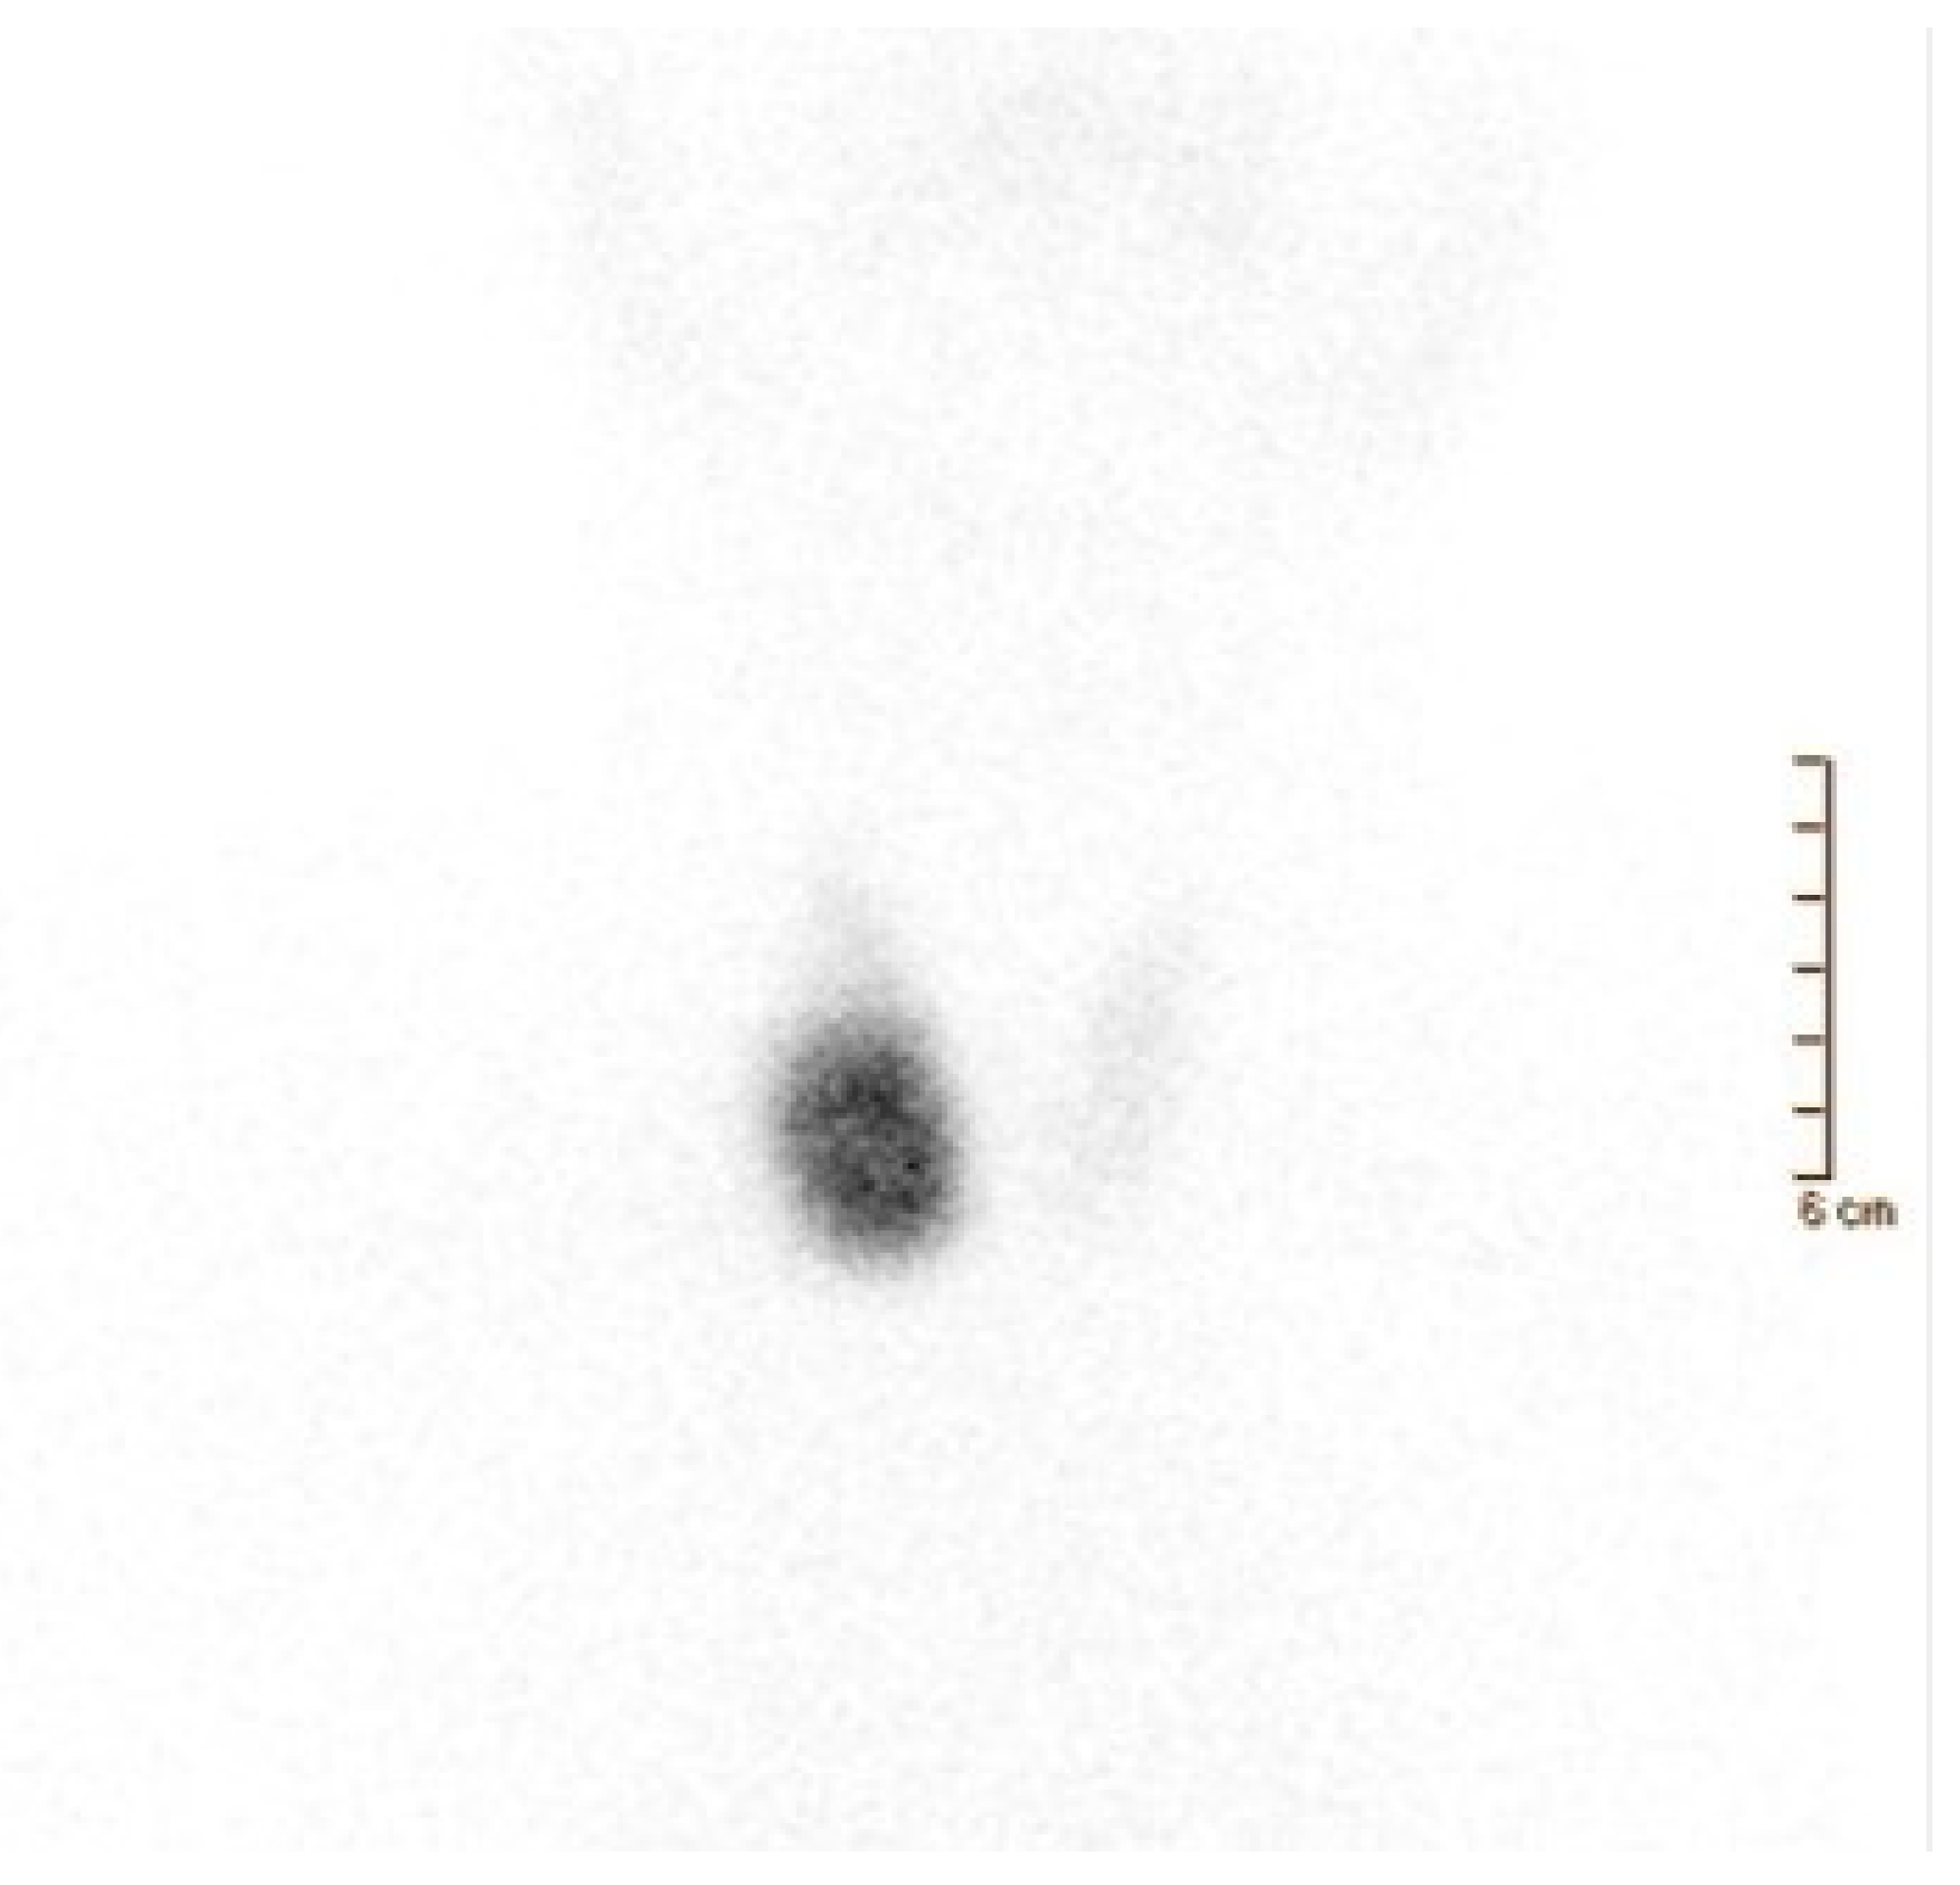

- Giovanella, L.; Campenni, A.; Treglia, G.; Verburg, F.A.; Trimboli, P.; Ceriani, L.; Bongiovanni, M. Molecular Imaging with (99m)Tc-MIBI and Molecular Testing for Mutations in Differentiating Benign from Malignant Follicular Neoplasm: A Prospective Comparison. Eur. J. Nucl. Med. Mol. Imaging 2016, 43, 1018–1026. [Google Scholar] [CrossRef]

- Campennì, A.; Giovanella, L.; Siracusa, M.; Alibrandi, A.; Pignata, S.A.; Giovinazzo, S.; Trimarchi, F.; Ruggeri, R.M.; Baldari, S. (99m)Tc-Methoxy-Isobutyl-Isonitrile Scintigraphy Is a Useful Tool for Assessing the Risk of Malignancy in Thyroid Nodules with Indeterminate Fine-Needle Cytology. Thyroid 2016, 26, 1101–1109. [Google Scholar] [CrossRef]

- Campennì, A.; Siracusa, M.; Ruggeri, R.M.; Laudicella, R.; Pignata, S.A.; Baldari, S.; Giovanella, L. Differentiating Malignant from Benign Thyroid Nodules with Indeterminate Cytology by 99m Tc-MIBI Scan: A New Quantitative Method for Improving Diagnostic Accuracy. Sci. Rep. 2017, 7, 6147. [Google Scholar] [CrossRef]

- Schenke, S.A.; Campennì, A.; Tuncel, M.; Bottoni, G.; Sager, S.; Crncic, T.B.; Rozic, D.; Görges, R.; Özcan, P.P.; Groener, D.; et al. Diagnostic Performance of 99mTc-Methoxy-Isobuty-Isonitrile (MIBI) for Risk Stratification of Hypofunctioning Thyroid Nodules: A European Multicenter Study. Diagnostics 2022, 12, 1358. [Google Scholar] [CrossRef]